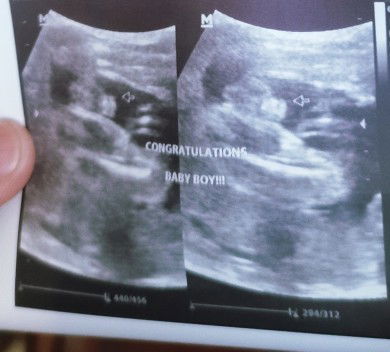

Boy gender?

Hello po. Can anyone help me confirm if boy po talaga gender ni baby? FTM anxiety strikes, sa dami ng nababasa kong nagkakamali. Hindi palang kasi makapag pa-ultrasound ulit to make sure. Kating-kati na ako mamili ng mga gamit.😅 Thank you po! #FTM #Marchbaby